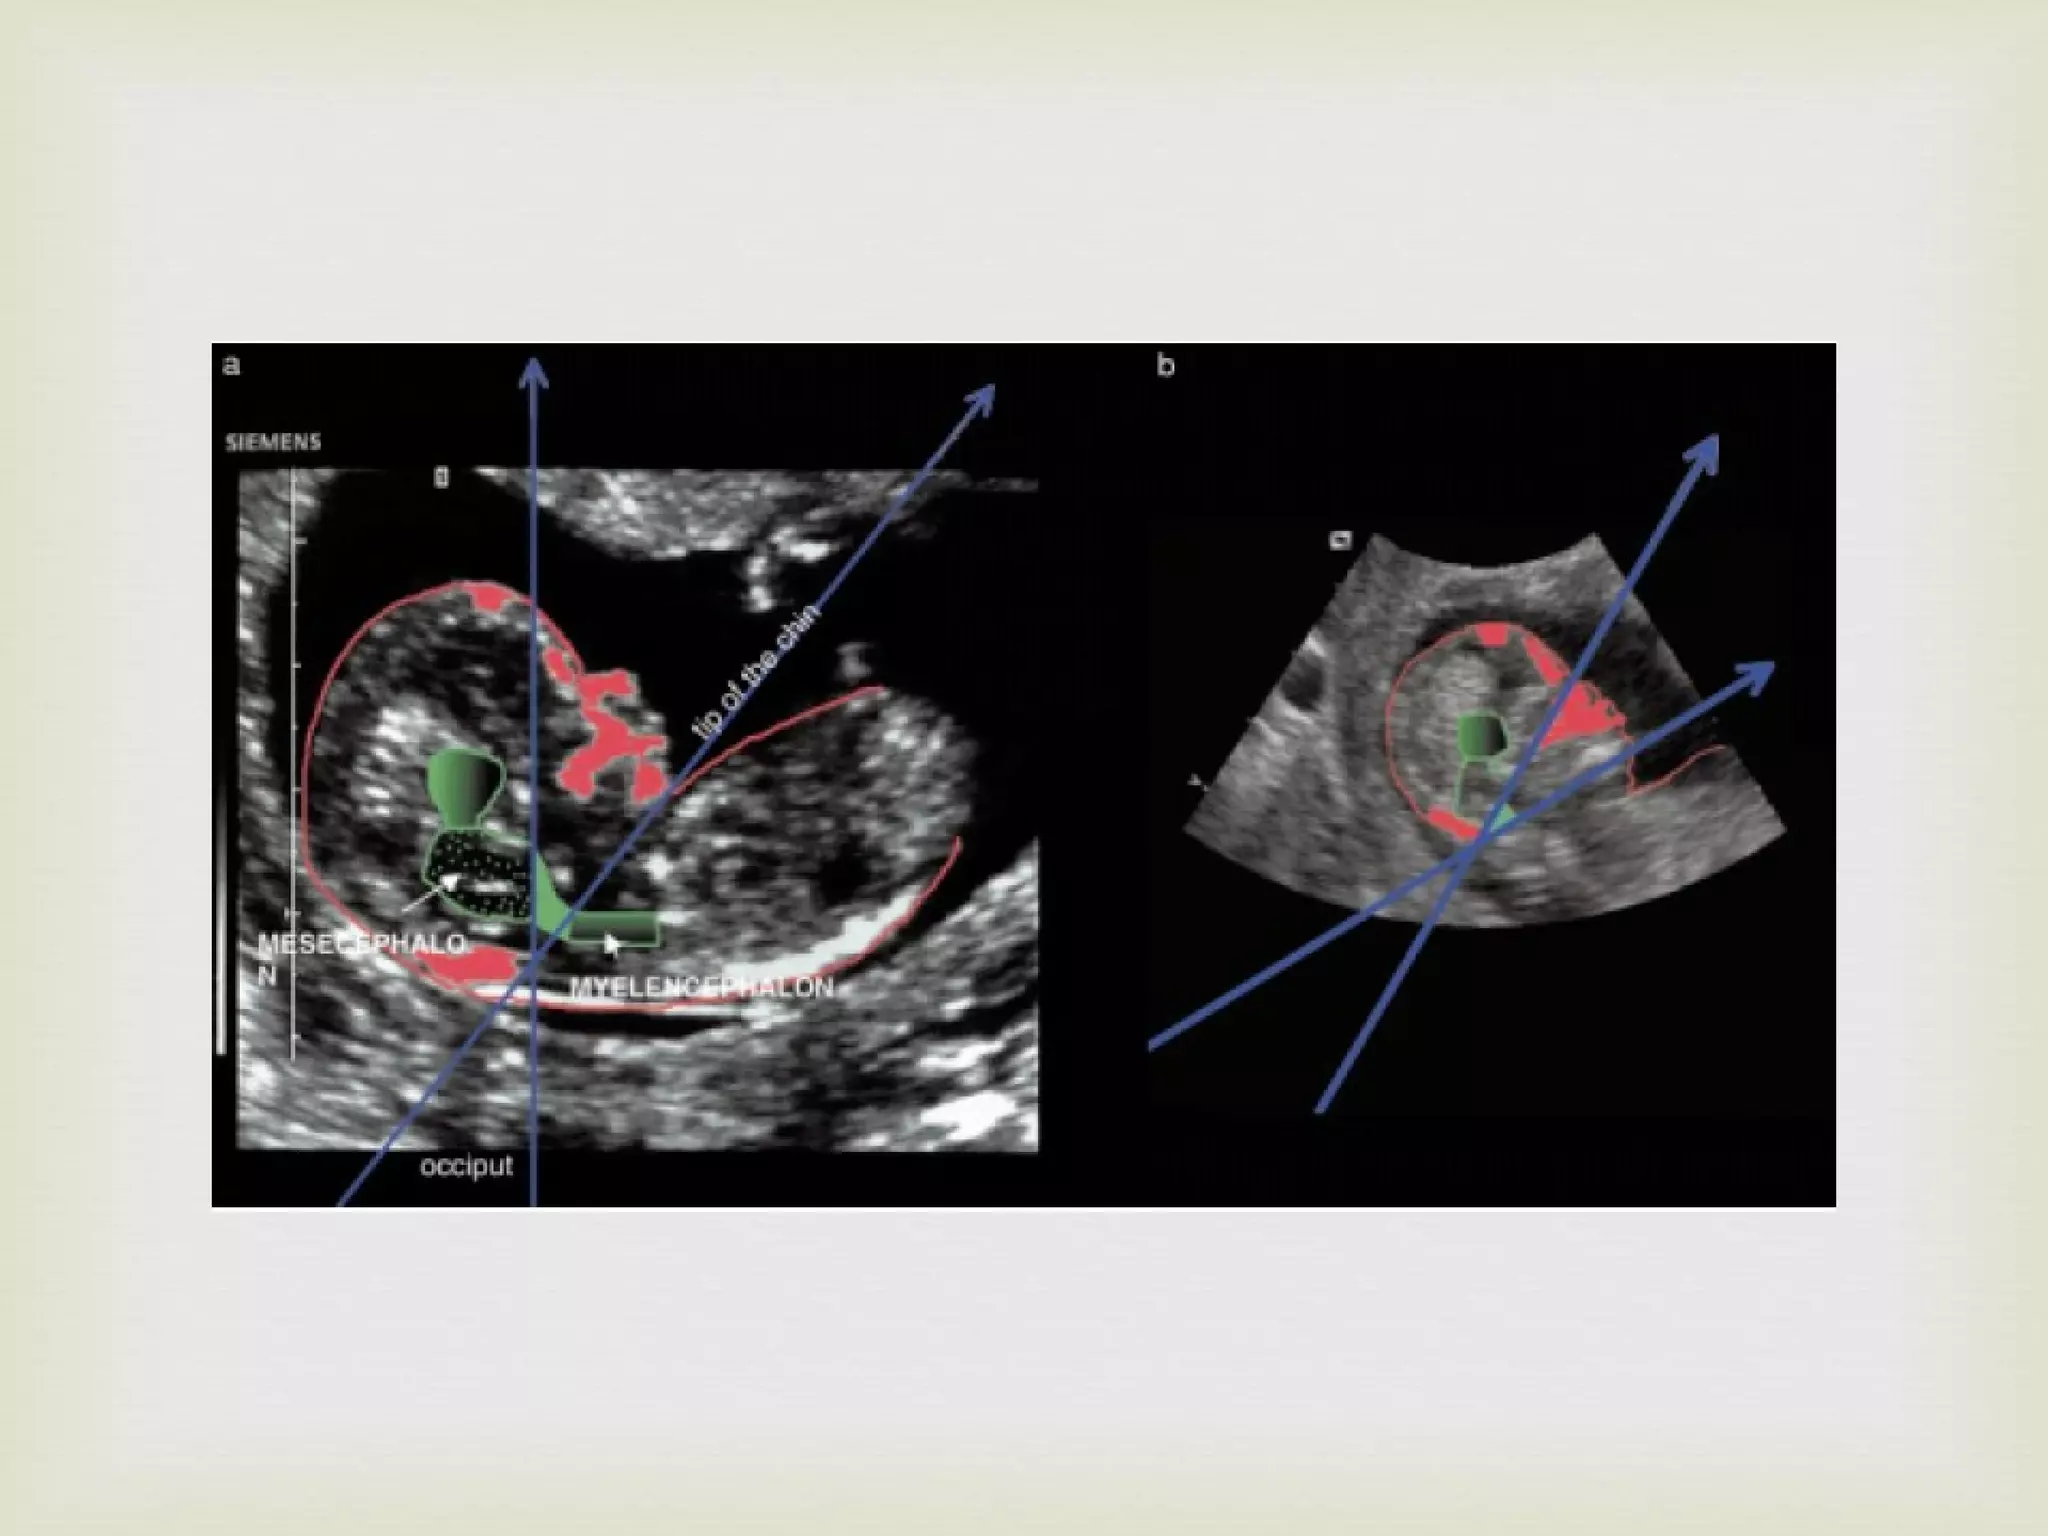

Acorn shaped head Small HC Parallel Cerebral Peduncles

The position of  parallel peduncles  is visible Visualisation of cerebellum  is difficult before 14 weeks  & may be confused with choroid plexus of the IV ventricle In sagittal view, the fetuses demonstrated a  flat occiput In axial view, the frontal bones are not convex but were retracted giving “acorn shape”

The contours of the metencephalon in spina bifida are straighter than normal This could be due to downward displacement of the brain

1 st  Trimester Equivalent of Banana sign

Distance between posterior border of Aqueduct of Sylvius and anterior border of Occiput in Axial Plane AOS-to-Occiput Distance

In cases with spina bifida, juxtaposition of the midbrain to the occiput was a clue to the diagnosis In all the cases AOS-to-occiput distance was below the established normal range In contrast to subtle changes in the sagittal view, axial imaging of the midbrain reveals striking changes which can be quantified by AOS-to-occiput distance